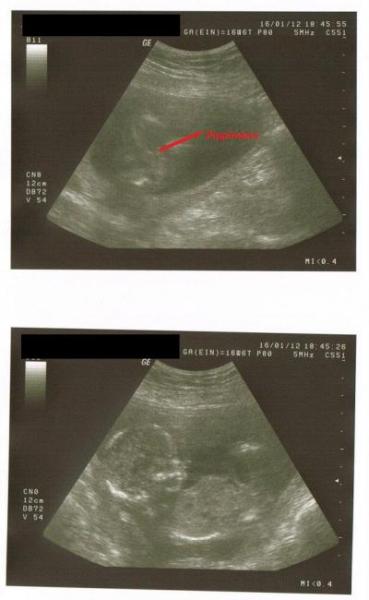

Guten Morgen meine Lieben, gestern hatte ich endlich meinen laaaang ersehnten Termin bei meiner Frauenärztin. Natürlich dabei der werdende Papa *freu* Ich wurde wie immer gewogen, musste Urin abgeben und der Blutdruck wurde gemessen. Fazit: Blutdruck supi, Urin "sauber" und Waage etwas besser. Bin seit heut in der 18. Woche und habe in den letzten 4 Wochen ganze 300g zugelegt. Dennoch ein Minus von rd. 4 Kg :D So kanns gerne weiter gehen. Dann kam das Beratungsgespräch und sie informierte sich über meinen Zustand und mein Wohlbefinden. Leider hab ich in der letzten Woche Besenreiser an den ganzen Beinen bekommen, so dass ich jetzt Sexy Kompressionsstrümpfe verschriben bekommen habe :) Mein Mann hat sich halb tot gelacht und gefragt, ob ich die jetzt für immer tragen müsste :D Dann hat sie mir einen Abstrich und Ultraschall gemacht. Auch der Abstrich war gut und dann hat sie uns angeschaut und gefragt, ob wir wissen möchten, was es wird. Wir haben direkt große Augen bekommen und sie sagte, dass sie einen Verdacht hätte :D "Da ist noch was Anderes, als die Nabelschnur" :D Dann wollte sie genauer schallen, aber das Kleine hat die Beinchen zu gemacht. Aber als erfahrene Frauenärztin hat sie - zu dem Zeitpunkt noch ES - ausgetrickst und von Richtung Kopf (vom Kind) über den Bauch geschallt. Und was war dort definitiv zu erkennen? 2 Hoden und ein Schniedel *freu* Also es wird ein Junge und sie sagte, dass sie sich schon ziemlich täuschen müsste, damit das nicht stimmt. In 4 Wochen hab ich das 2. große Screening und dann macht sie das ganze auch in 3D, damit man es nochmal besser erkennen kann :) Zum Schlus wurde mir nochmal Blut abegenommen, damit meine Eisenwerte überprüft werden können und ich hab eine Menge Infomaterial bekommen. So, ist ganz schön lang geworden :) Achso, seit heute bin ich dann auch in der 18. Woche :) Lg Trice

Bild zu Gestern FA-Termin mit Outing :) - Forum für Juni - Mamis